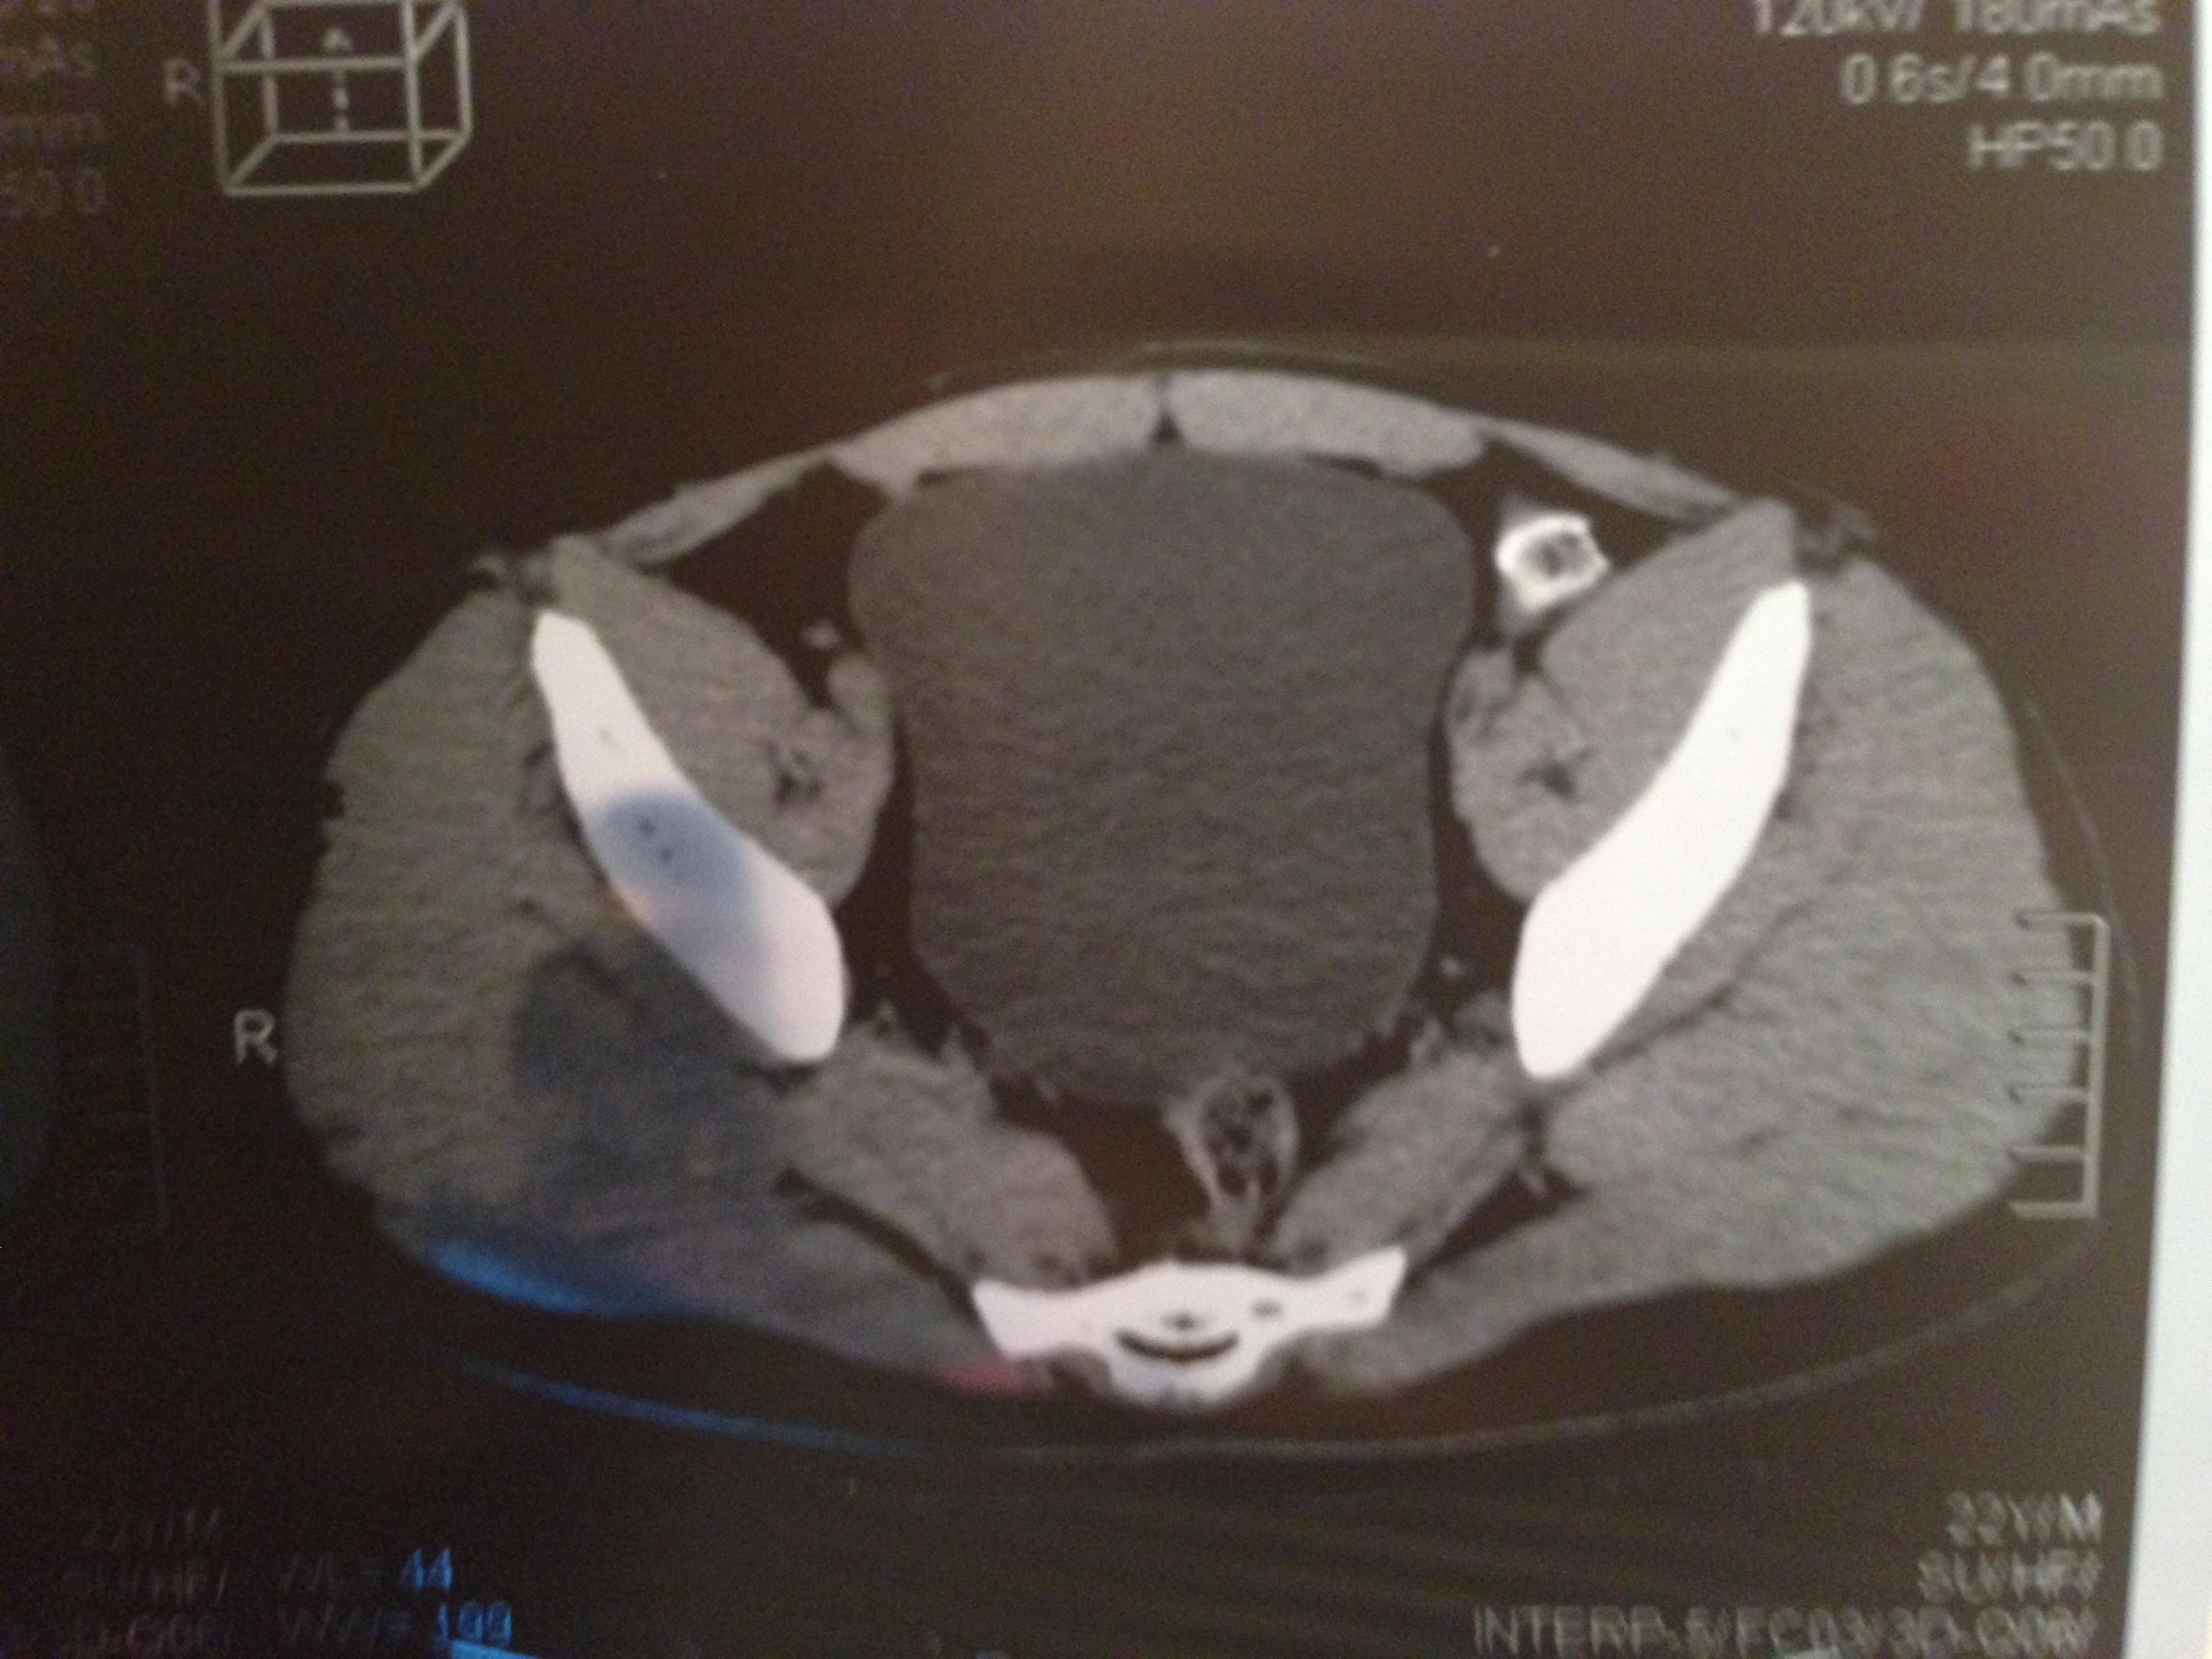

проведена МСКТ области таза!Внеорганных дополнительных патологических образований,лимфаденопатии или свободной жидкости в области таза не выявлено.

Мочевой пузырь-наполнен,стенки не утолщенны,паравезикально-без грубой органки.

Граница между предстательной железой и пузырем несколько четкая,контур пузыря на данном уровне не деформирован.

Предстательная железа-без грубой органики,еденичные микрокальцинаты.

Семенные пузырьки-конфигурация не совсем типична,примерный размер правого 26*28мм.Отмечаются признаки кистовидной трансформации и микрокальцинации обоих пузырьков.Наибольшая из кист слева достигает 9 мм.Обращает на себя внимание неравномерная кальцинация стенок крупных регионарных(текстикулярных)артерий с обоих сторон.

Костно-деструктивных изменений характерных для mts со стороны костей таза не отмечено.

Параректальная клетчатка-не изменена,патологически увеличенных лимфоузлов в параректальном пространстве не отмечено.M.m.levator ani-без особенностей.

Заключение:на момент исследования,КТ-данных за наличие внеорганных дополнительных патологических образований,лимфоденопатии или свободной жидкости в области таза не выявлено.КТ-признаки в пользу проявлений калькулезного везикулита с элементами кистовидной трансформации семенных пузырьков.